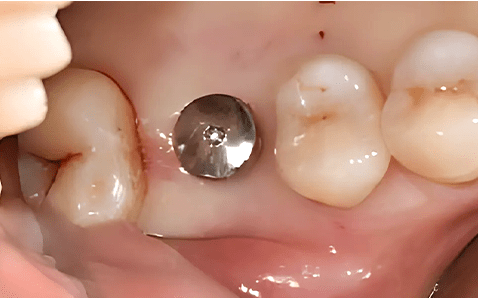

Case 01

임플란트 식립 전 절개없는 임플란트 식립 직후

촬영시기 : 2024.12.05